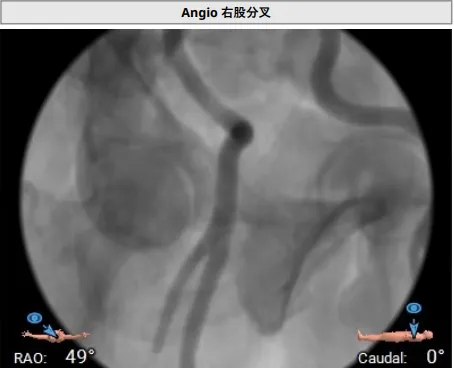

右侧股动脉分叉位置可

TAVR手术过程

主动脉瓣大量反流

回撤导引鞘,定位键顺利展开

输送器调弯

定位键解离

推送入窦形态改变不明显

无窦瓣叶脱垂影响瓣叶夹持

回撤后增加调弯夹持瓣叶

右窦中心造影确认瓣叶夹持

食道超声确认瓣叶夹持

经胸超声确认右冠瓣叶夹持

回撤MP导管,一键释放瓣膜

松弯后输送器回撤至大鞘,更换小鞘

术后右窦中心造影,无漏,无AVB